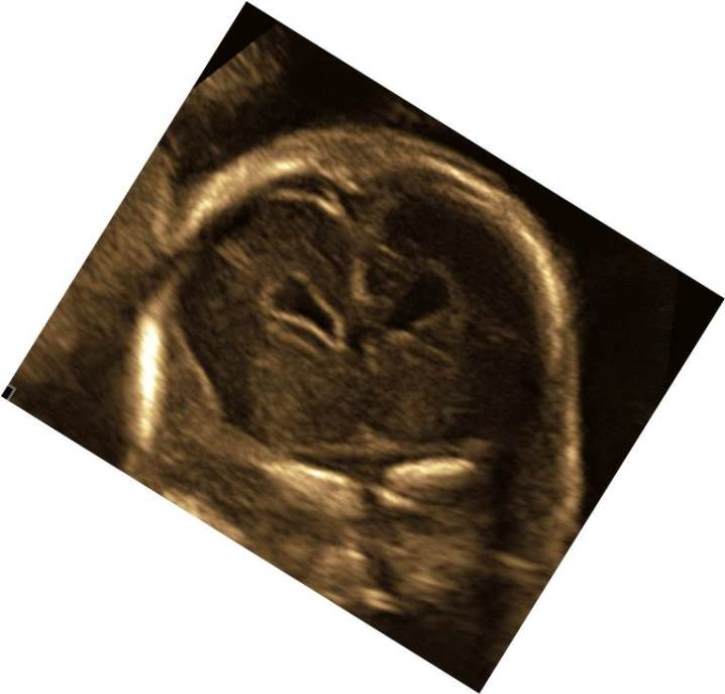

Коронарный скан. В каком из случаев высока вероятность перивентрикулярной нодулярной гетеротопии (ПНГ)?

Ответ на вопрос 1

- В передней части передние рога разделены, но полость прозрачной перегородки отсутствует — она облитерирована. В задних отделах отсутствует прозрачная перегородка. Повышенная эхогенность и неровность контура в области герминогенного матрикса. Неровность контура бокового желудочка по всему периметру, перивентрикулярная повышенная эхогенность.

- Диагноз: мальформация коры головного мозга- перивентрикулярная нодулярная гетеротопия, частичная агенезия прозрачной перегородки, высока вероятность кровоизлияния 1 ст в области герминогенного матрикса